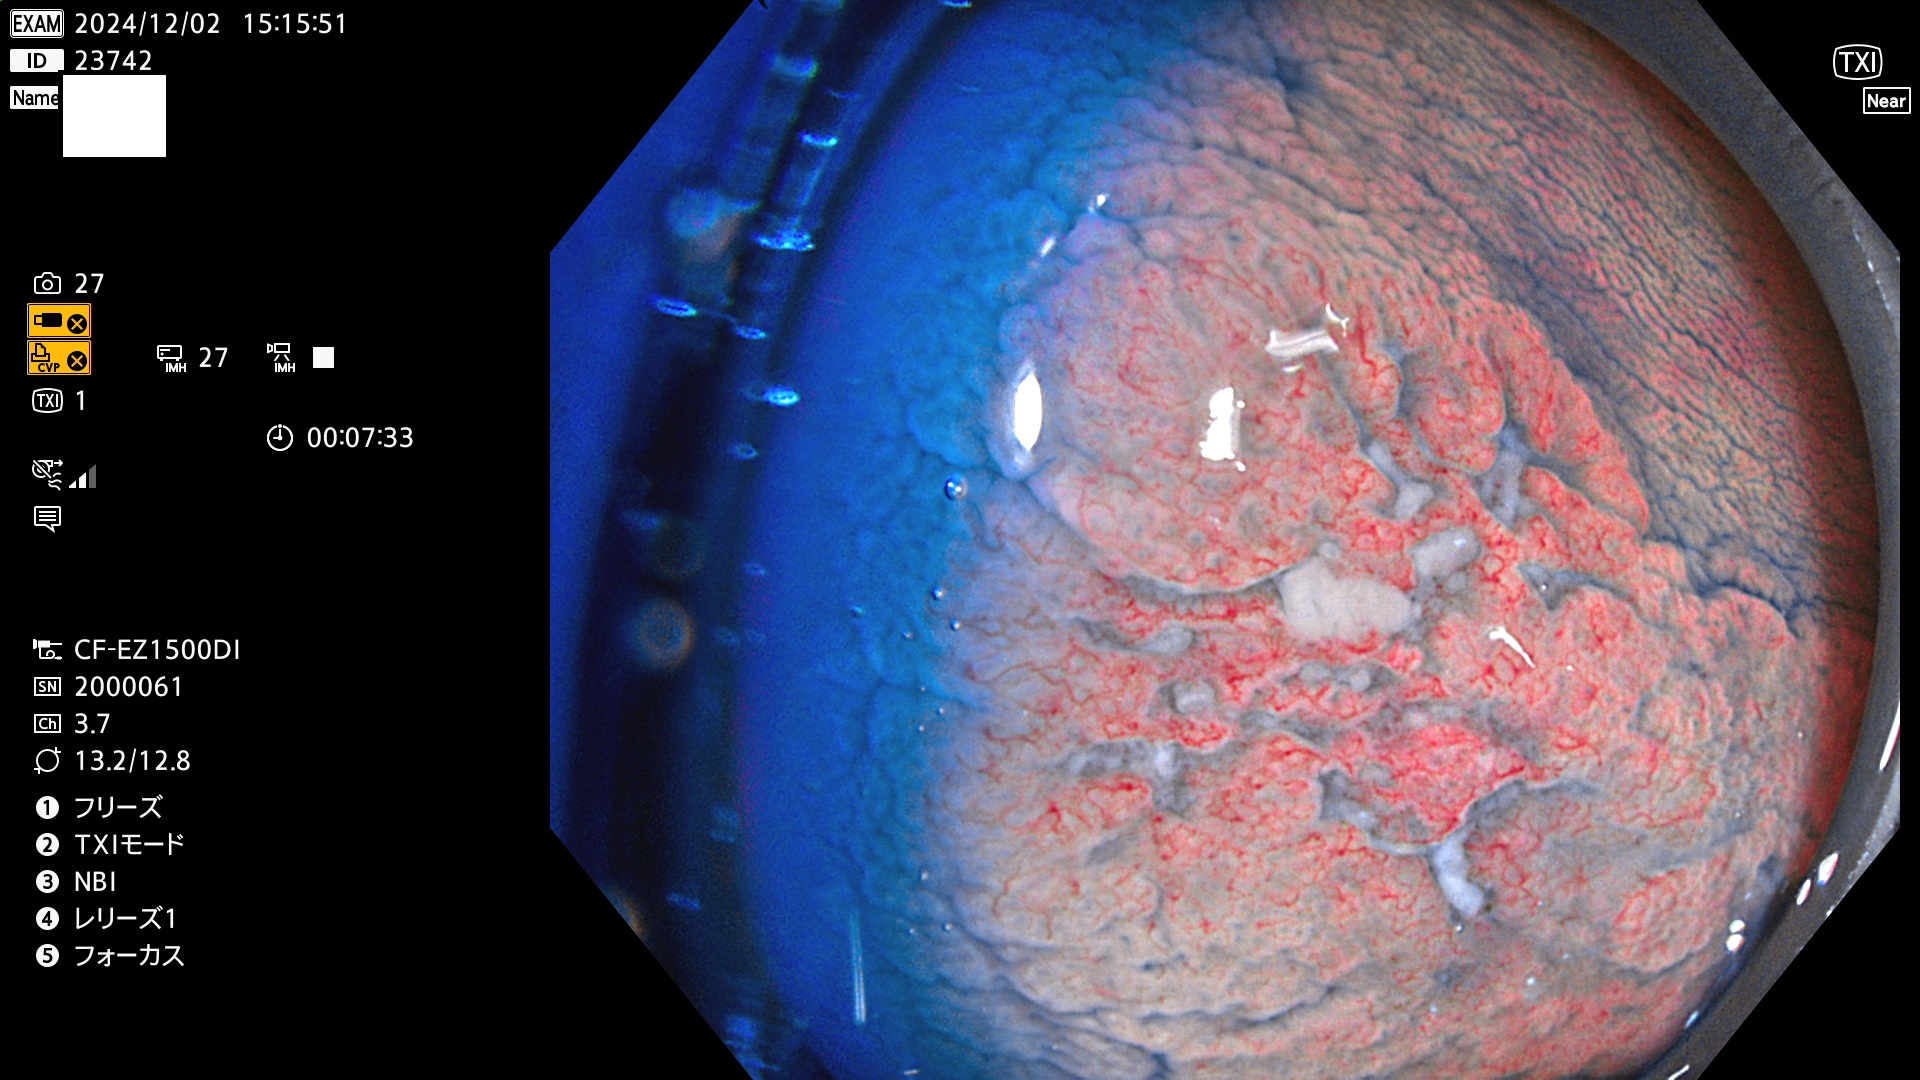

完全に平坦な物をUb、陥凹している物をUcと呼びます。最も発見が難しく危険な病変です。

毎週の検査(木・金・土・日)に発見されたUb、Uc型・腺腫を、その週の日曜の夜にUPし1週間、提示します。

抽出の対象期間 2024年11月28日〜12月2日の5日間(60件の検査)9件 (9/60=15%)